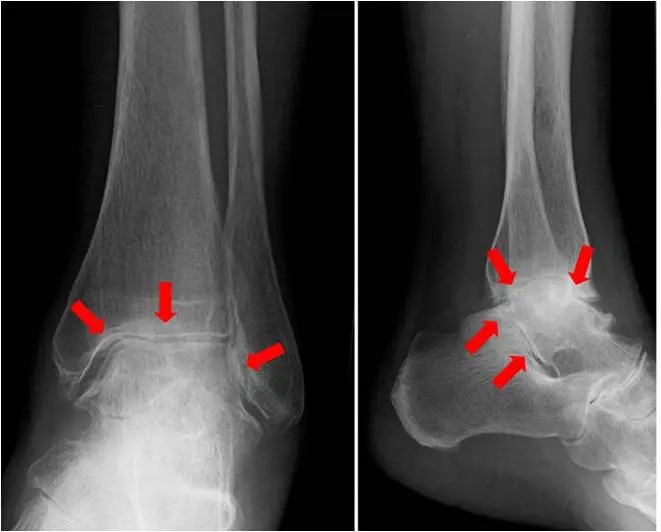

Das Röntgenbild des Sprunggelenkes in zwei Ebenen im Stand zeigt in fortgeschrittenen Fällen typische Arthrosezeichen:

• Gelenkspaltverschmälerung

• subchondrale Sklerosierung

• Exophyten

• Deformierung des Gelenkes

Röntgenbild einer OSG Arthrose mit starker Verschmälerung des Gelenkspalts

welche stadienabhängig unterschiedlich stark ausgeprägt sind.

Spezialaufnahmen wie die Saltzman-Aufnahme oder Rückfußaufnahme können helfen die Rückfußachse zu beurteilen. In fortgeschrittenen Fällen und zur präoperativen Planung ist ggf. eine Schnittbildgebung in Form eines CT oder MRT sinnvoll,.